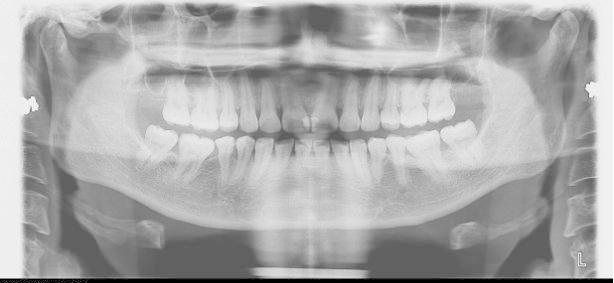

首先我们看能不能矫正,不是单纯靠年龄来判断,并不是年龄大的就不能矫正,年龄小的就一定能做。限制牙齿移动的关键不是年龄,而是牙周的健康状况。当然,除了牙周的健康程度外,我们还得考虑牙齿的健康程度、关节的健康程度,以及配合度等问题。在排除以上问题后我们还是建议大家尽早解除自己的牙齿问题的。

疗效问题

年龄虽然不是限制整牙的关键因素,但成人矫正还是有自身限制的。成人毕竟不像小朋友一样,有非常旺盛的生长潜力,那么我们成年人治疗的目标有时相对而言就要放得保守一点,尤其对有骨性问题,牙周不那么健康,关节不那么健康的人而言就不能事事追求完美。